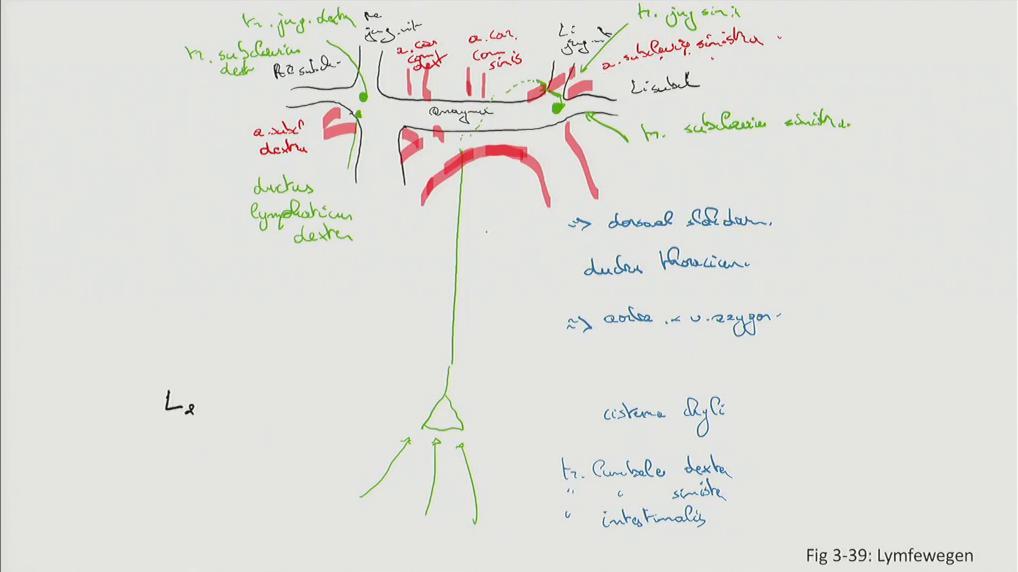

Fig 3.39: Lymfewegen

-

arcus aortae

v brachiocephalica sinistra = v anonyma v subclavia dextra v jugularis interna dextra v jugularis interna sinistra v subclavia sinistra -

ductus thoracicus (groen)

truncus jugularis sinister truncus subclavius sinister truncus jugularis dexter truncus subclavius dexter ductus lymphaticus dexter

Sobotta: Fig 5.25